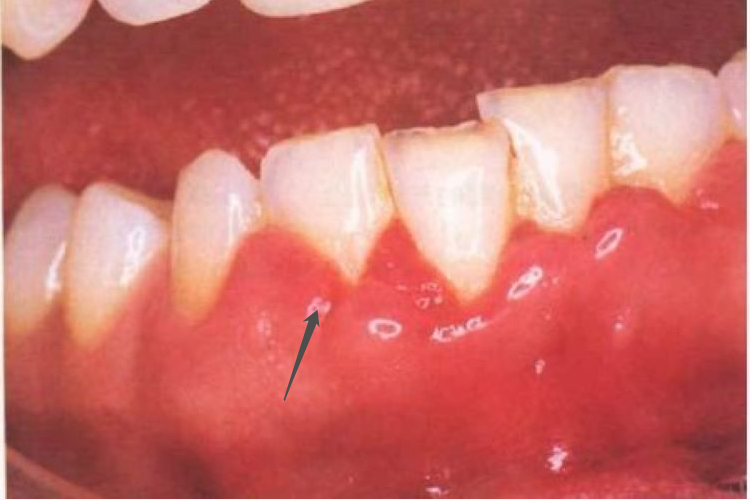

牙龈炎:正常牙龈呈粉红色,牙龈炎可表现为鲜红或暗红色,常在刷牙或咬硬物时牙龈出血。部分患者可感到牙龈局部痒、胀等不适症状。